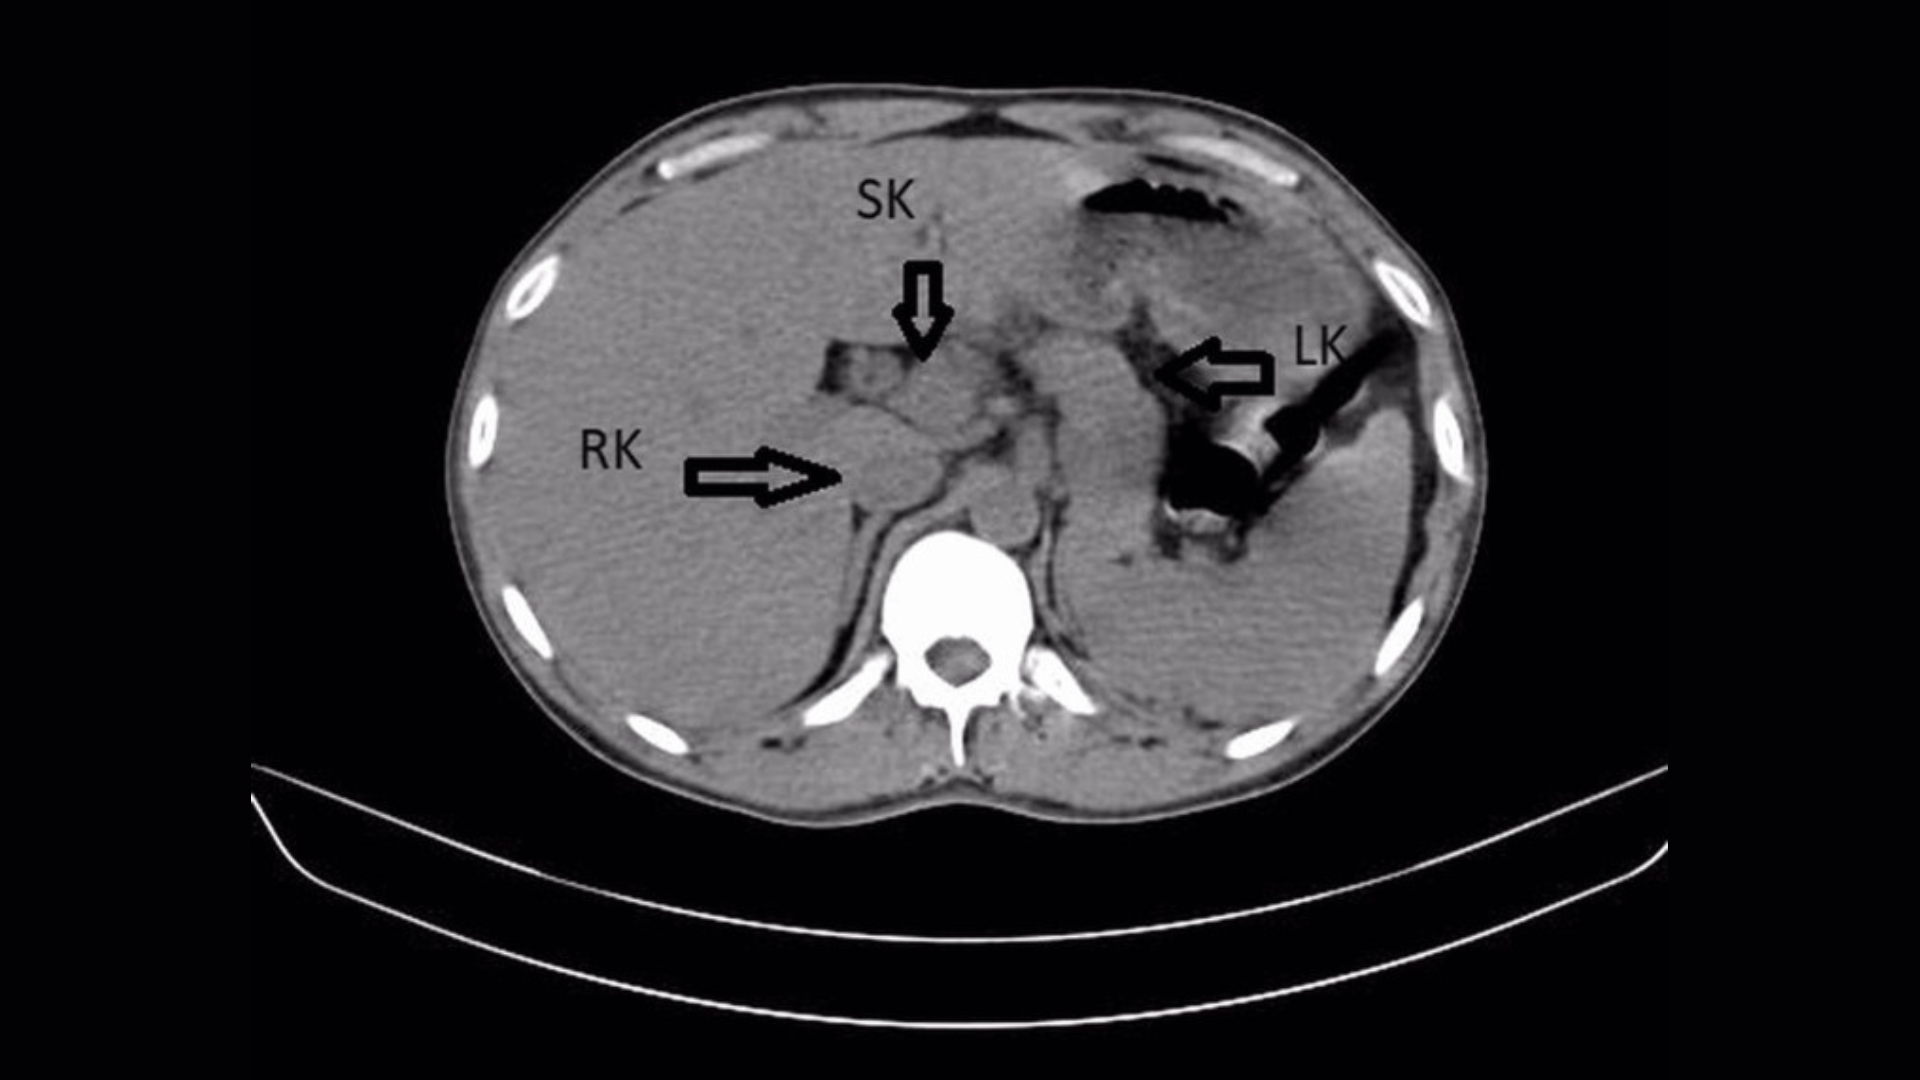

However, advanced medical imaging of the patient’s abdomen, specifically an ultrasound and a CT scan, uncovered a truly unexpected anatomical anomaly. Scans revealed the presence of a third kidney—medically termed a supernumerary kidney—which was remarkably fused with the man’s existing right kidney, creating a distinctive horseshoe shape.

**A highly unusual kidney formation, resembling a horseshoe shape, has been documented in the scientific literature only five times, making it an exceptionally rare anomaly.** In other instances, a third kidney may develop as an entirely independent organ or be connected to another kidney by a delicate membrane.